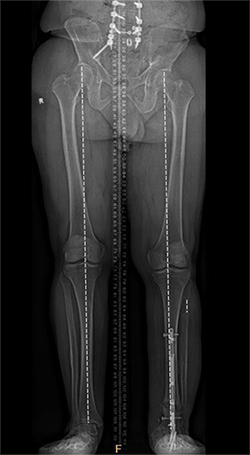

Guy Natale X-ray after leg lengthening.

The operation took place in November 2022. Because Natale’s ankle was fused, Marecek chose to lengthen Natale’s tibia, or shin bone, rather than his femur. Marecek also identified that Natale’s ankle had been fused out of alignment. So, first he corrected the ankle’s alignment, then he broke Natale’s tibia and inserted a distraction rod—the kind that could push the two sides of the broken bone apart.

Natale could not put any weight on the leg for three months. After that the distraction rod was removed and replaced by a weight-bearing rod.

Natale says he had to do a lot of physical therapy, stretching the muscles to make space for the longer leg bone. It was about six months before Marecek gave him the go-ahead to put his full weight on it. Even after a year, X-rays showed the bone still hadn’t completely filled in the gap around the rod in his tibia.